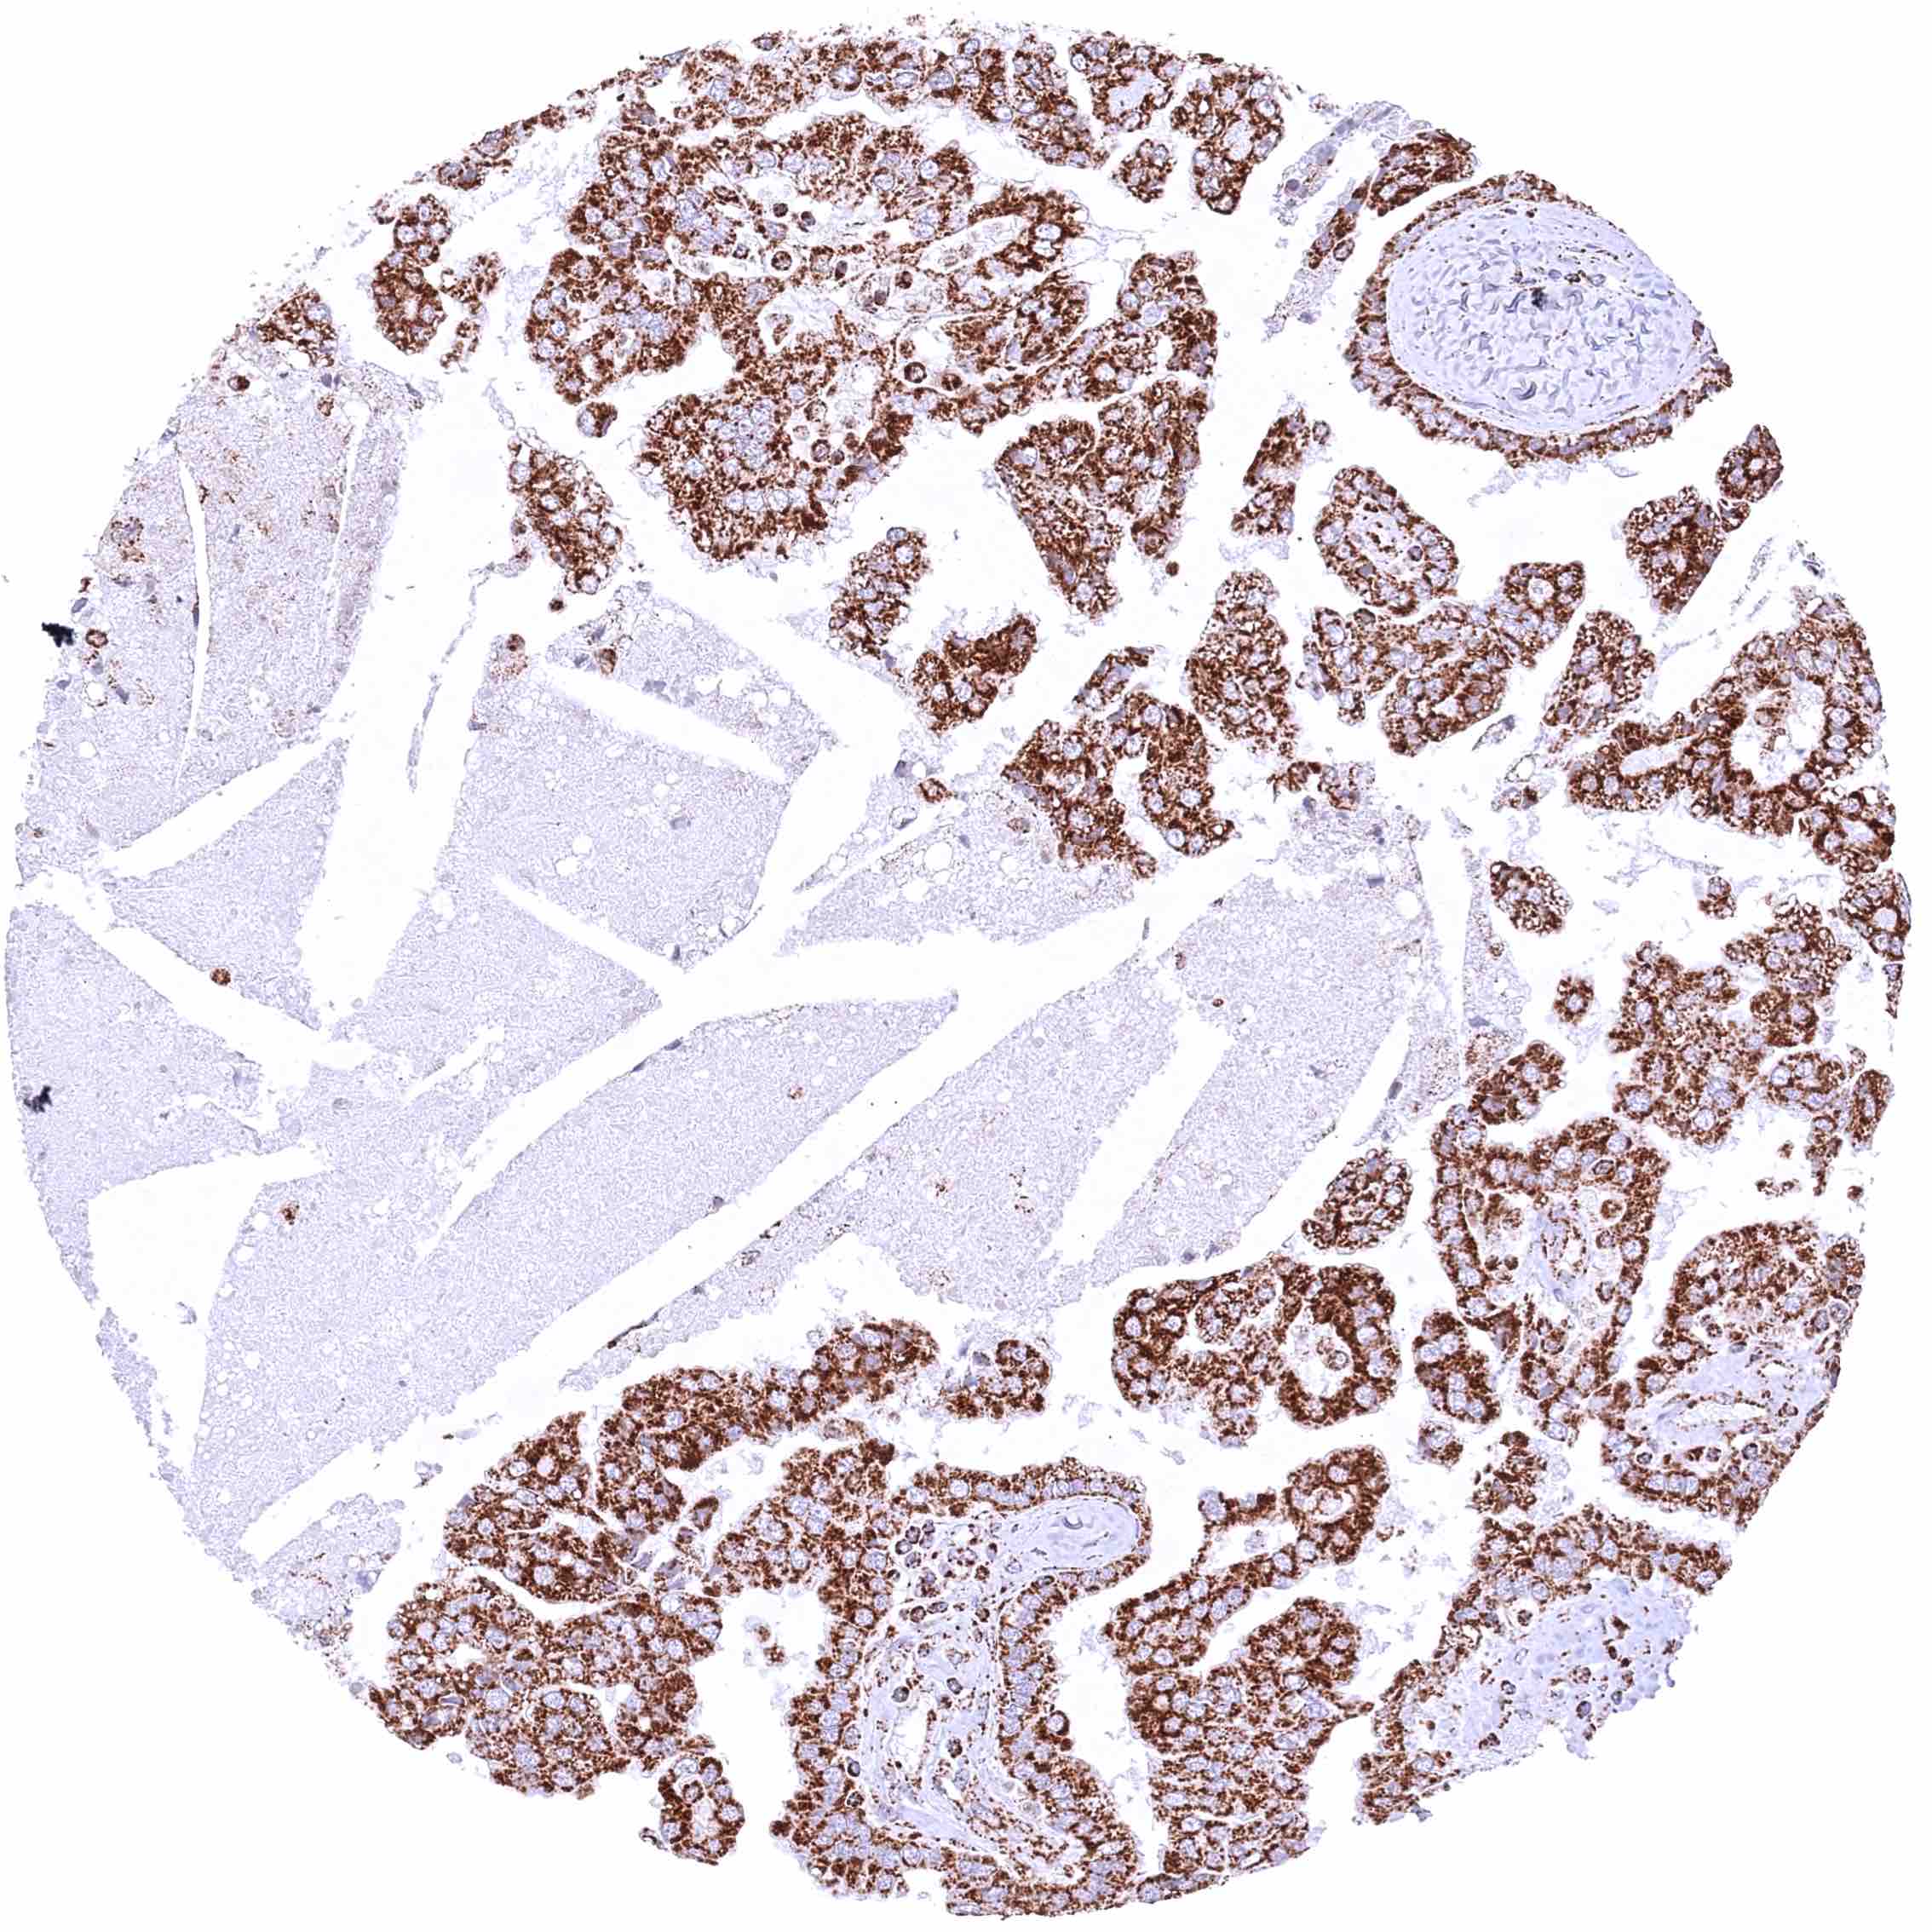

Ovary – Clear cell carcinoma with strong cytoplasmic ATP5J staining of tumor cells.